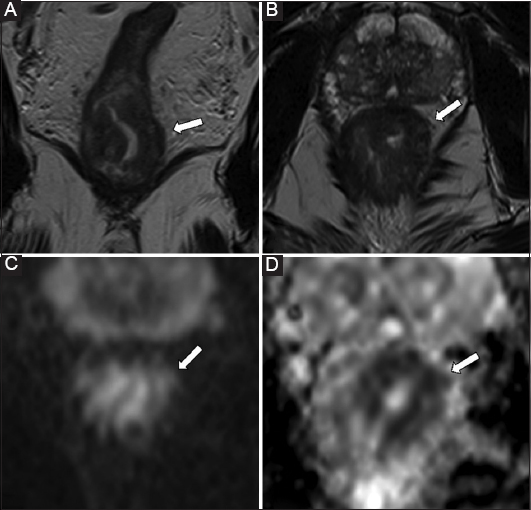

Based on our experience, in 14% of patients, T2-weighted imaging was not successful in differentiating perirectal inflammation from tumor invasion, resulting in overstaging (Fig. 2). Notably, our failure rate is consistent with the level of overstaging reported in a previous study on T3 tumors, which ranged from 11-16% [6]. Several studies have emphasized this limitation, highlighting the technical inability of T2-weighted imaging alone to reliably discriminate a desmoplastic reaction from tumor infiltration into the mesorectal fat [13,21,32,37-40]. In our series, all overstaged cases exhibited linear or band-like signal abnormalities within the mesorectal fat, which were interpreted by both readers as early signs of extramural tumor invasion. However, it is well established that MRI cannot effectively distinguish desmoplastic reactions from true extramural tumor infiltration, particularly in the absence of a nodular morphology [38]. In contrast, DWI had promising results in the characterization of peritumoral tissues, compared with conventional MRI, taking advantage of tumor hypercellularity. In the current study, DWI exhibited a high diagnostic performance across all tumor stages, achieving superior sensitivity and specificity (91.43-100%) compared with conventional MRI. These findings are consistent with those of previous studies [30,32,37]. However, they provide a novel perspective. In particular, the adjunctive use of DWI had remarkable accuracy in early-stage (T1-T2) tumors, which are traditionally considered challenging to stage using MRI [13]. Based on our experience, the addition of DWI significantly improved the sensitivity of conventional MRI, particularly for assessing T2 and T3 tumors, which are critical stages in determining the most appropriate treatment strategy (Fig. 3). This improvement may contribute to a reduction in overstaging, thereby sparing more patients from unnecessary presurgical chemotherapy. In our cohort, DWI (97.01%) had a higher sensitivity for T3 tumor staging than conventional T2-weighted sequences (91.43%), indicating an excellent positive predictive value. To the best of our knowledge, previous studies have not assessed the potential of DWI for predicting T3 stage with such high accuracy, nor have they included such a large patient cohort. Notably, only 1 recent study, which included a cohort of 81 patients, showed that DWI had a good predictive value in evaluating the depth of muscularis propria invasion in mid- to high-rectal cancers, emphasizing its potential utility in preoperative staging [41]. However, the study used a purely quantitative DWI approach, relying on the manual assessment of ADC map values, which may limit its generalizability in clinical practice. In our opinion, this technique is labor-intensive, prone to interscanner variability, and strongly influenced by distortion inherent to DWI that may influence the precision of ROI boundary assessment. By contrast, our study used a more practical and reproducible approach, which is in accordance with routine clinical practice, based on the qualitative assessment of DWI signal characteristics and T2-weighted imaging, without the need for segmentation or quantitative mapping.

thumblarge

Figure 2 A 78-year-old patient with histologically confirmed rectal adenocarcinoma. Coronal (A) and axial (B) high-resolution T2-weighted images (with a slice thickness of 3 mm) showing a heterogeneous tissue mass involving the right hemicircumference of the mid rectum, with diffuse inhomogeneity and spiculated extensions (length 5 mm), raising suspicion for mesorectal fat invasion (T3c stage). Axial diffusion-weighted imaging (C) and the corresponding apparent diffusion coefficient map (D) depicting clearly hypercellular pathological tissues confined within the rectal wall, without evidence of invasion into the adjacent mesorectal fat. Final histopathological analysis confirmed an intramural tumor (stage pT2)